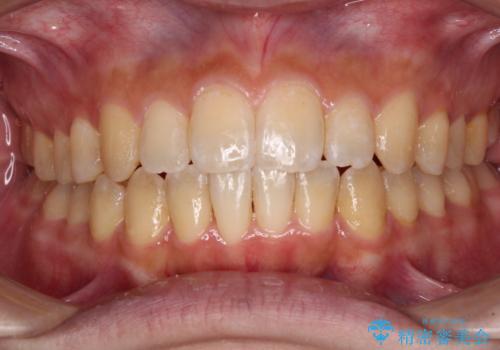

- 奥歯の詰め物が外れてしまったとのことで来院された患者様です。

幾度も詰め物治療を行ったため継ぎ接ぎだらけとなっていたため、インレーにて修復治療をすることとしました。

咬合力が強いため、ゴールド合金(PGA)のインレーを選択することとしました。

咬み心地はとても良好で、全く違和感がなく、患者様には大変満足していただきました。